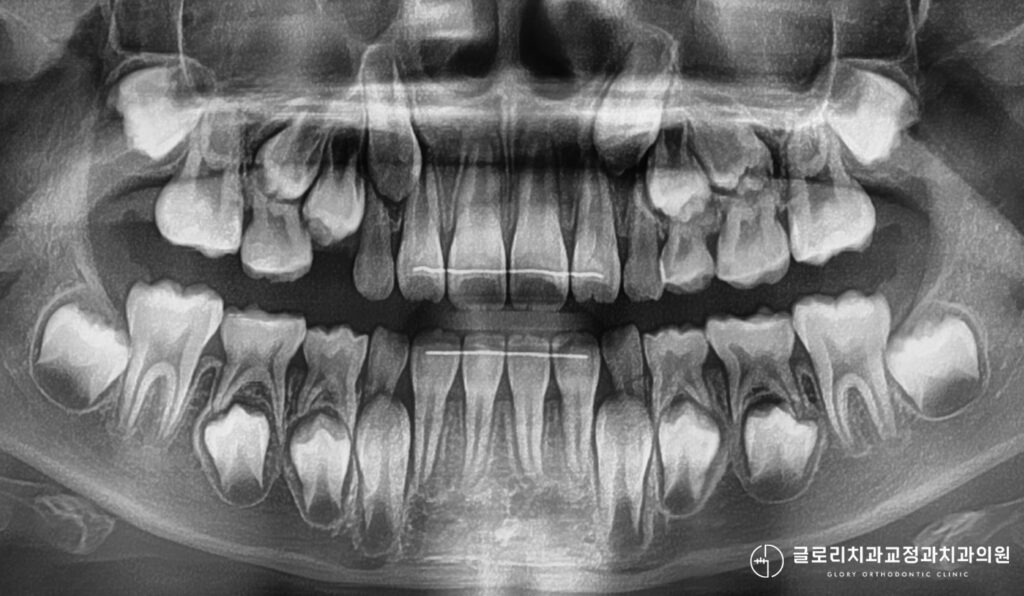

우선 어린이 교정은 어른들과 달리 성장 시기를 고려해야 하므로 정밀한 검사가 선행됩니다.

성인 교정 상담에서는 치아 배열과 교합 상태를 중점적으로 살펴봅니다.

반면 어린이 상담 과정에서는 골격 성장 정도를 파악하는 성장판 검사가 포함됩니다.

손목 X-ray 촬영을 통해 수완부 골성숙도를 확인하면 아이의 뼈 나이를 알 수 있습니다.

실제 나이와 뼈 나이를 비교하면 현재 성장 속도가 빠른 편인지 느린 편인지 파악이 가능합니다.

이 정보는 단순히 참고용이 아니라 최적의 치료 시작 시점을 결정하는 핵심 자료가 됩니다.

턱뼈가 아직 성장 중이라면 그 힘을 활용한 치료가 가능하고, 성장이 거의 끝났다면 다른 접근 방식을 고려합니다.

아이의 구강 내부를 자세히 살펴보면 영구치가 나올 공간이 부족한 경우가 있습니다.

위아래 치아 사이에 맹출 공간이 협소하고 특히 입천장이 좁고 깊다면 상악골 확장 이 필요할 수 있습니다.

악궁은 치아가 배열되는 아치 형태의 뼈 구조로, 이 공간이 좁으면 치아들이 서로 밀리며 덧니가 생깁니다.

1차 교정이 마무리되어도 영구치 맹출이 진행 중이라면 정기적인 관찰이 필요할 수 있습니다.

이 시기에는 정기적인 내원을 통해 영구치 맹출 상태와 교합 변화를 관찰합니다.

1차교정이 마무리되면 앞으로 나올 영구치들의 자리가 어느정도 확보되면서 가지런하게 정돈됩니다.

이후 모든 영구치가 맹출을 완료하면 2차 교정 필요 여부를 다시 평가하게 됩니다.

1차 교정으로 공간을 확보하고 앞니를 배열했더라도 전체적인 교합 조정이 필요할 수 있습니다.

다만 1차 교정을 통해 골격적 문제를 미리 개선했다면 2차 교정의 난이도나 기간이 줄어들 가능성이 있습니다.